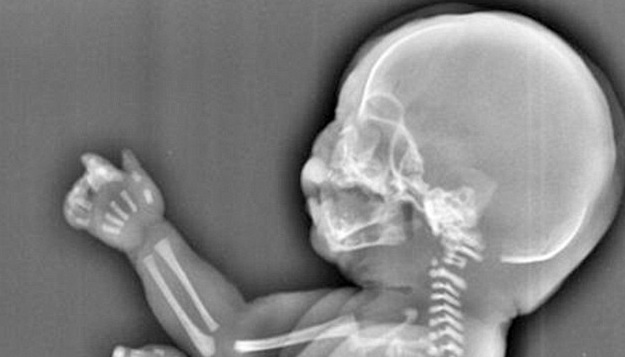

La mujer se hizo un escáner que revelaba que su hija no tenía dos piernas, sino que como un tipo de cola creciendo, pero eso no era todo, pues la pequeña tampoco tenía vejiga, y el hígado tenía un retraso en su crecimiento.

De acuerdo con Daily Mail, los doctores dijeron que su feto estaba sufriendo de una condición conocida como el “síndrome de la sirena” o “sirenomelia”, que es una deformidad congénita donde sus piernas crecen unidas, es decir, como solo una, lo que daría una apariencia del místico personaje.

El medio inglés explica que los casos de “síndrome de la sirena” son un misterio médico y que solo ocurre en uno de 100 mil embarazos. Siendo fatal, pues casi no logran sobrevivir, y es que las complicaciones asociadas al desarrollo del riñón y la vejiga, terminan con la vida de los pocos bebés con sirenomelia que nacen vivos.